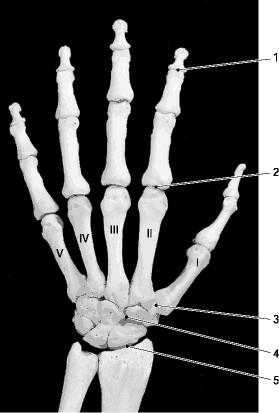

The intercarpal joints are the synovial plane joints that connect the carpal bones. They gather three sets of joints; Joints of the proximal carpal row, that connect the adjacent surfaces of the scaphoid, lunate and triquetrum bones.

Joints of the proximal carpal row, that connect the adjacent surfaces of the scaphoid, lunate and triquetrum bones. The pisiform joint, an articulation between the pisiform and triquetrum, is described as a separate joint but it belongs to the proximal carpal joints.

The pisiform joint, an articulation between the pisiform and triquetrum, is described as a separate joint but it belongs to the proximal carpal joints. Joints of the distal carpal row, via which the adjacent surfaces of the trapezium, trapezoid, capitate, and hamate bones articulate.

The radiocarpal joint is made up of four bones:

There are five CMC joints in total, out of which the carpometacarpal joint of thumb ( trapeziometacarpal joint) is the most specialized and flexible. The remaining four CMC joints are functional plane synovial joints that connect the medial four metacarpal bones (metacarpals 2, 3, 4, 5) with the distal row of carpal bones (trapezium, trapezoid, ...

What is the CMC of the hand?

Carpometacarpal (CMC) joints. The carpometacarpal (CMC) joints are articulations between the carpal bone s (carpo-) and metacarpal bones (-metacarpal) of the hand. There are five CMC joints in total, out of which the carpometacarpal joint of thumb ( trapeziometacarpal joint) is the most specialized and flexible.

Vertical section through the joints at the wrist, showing the synovial cavities. Ligaments of wrist. Anterior view. The intercarpal joints ( joints of the carpal bones of the wrist) can be subdivided into three sets of joints (also called articulations ): Those of the proximal row of carpal bones, those of the distal row of carpal bones, ...

What joint is between the metacarpals?

What are the bones that make up the wrist?

The carpal bones are a group of short bones [24] in the human hand that collectively forms the wrist, along with the distal ends of radius and ulna [1]. Collectively referred to as the carpus, they individually articulate with the long bones in the lower arm radius and ulna, as well as the metacarpals, to make up the wrist joint.